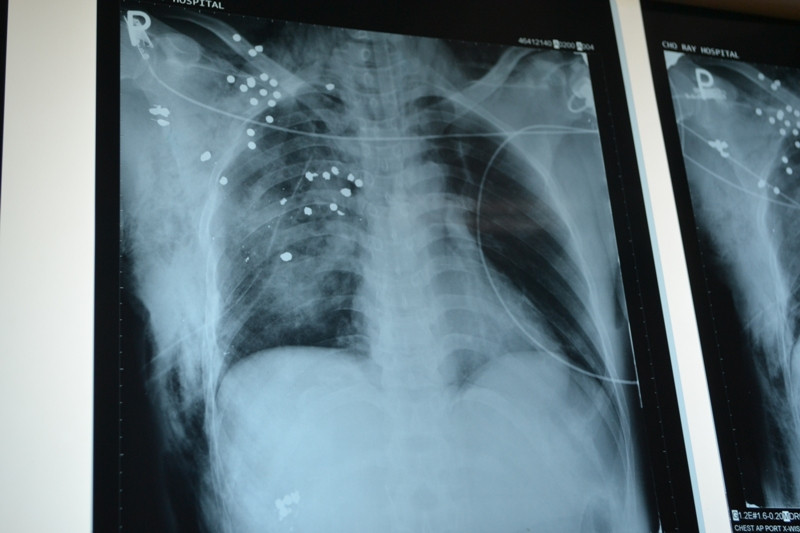

Nạn nhân Nguyễn Hoàng Nam đang điều trị sau phẫu thuật ở BV Chợ Rẫy. Ảnh L.N.

Chiều nay, 24/10 TS-BS Vũ Hữu Vĩnh- Trưởng Khoa Ngoại lồng ngực, Bệnh viện Chợ Rẫy xác nhận vừa phẫu thuật cứu sống bệnh nhân Nguyễn Hoàng Nam, 40 tuổi ngụ ở huyện Mộc Hóa, tỉnh Long An bị súng cướp cò bắn vào sườn phải. Trước đó, anh Nam nhập viện với vết thương khá nặng ở sườn phải, mất máu. Qua thăm khám và chụp CT scan, các bác sĩ phát hiện có khoảng 30 mảnh đạn hoa cải nhỏ li ti găm vào sườn, phổi. Ngoài ra, một nhánh sườn bên phải bị gãy nát, tràn khí màng phổi và máu tụ ở màng phổi phải.

Sau hội chẩn, ê kíp khoa Ngoại Lồng ngực đã tiến hành phẫu thuật gắp ra khoảng 8 mảnh đạn lớn, đồng thời cắt lọc vết thương, lấy hết máu tụ trong khoan màng phổi. “Hiện vẫn còn khoảng 20 mảnh đạn hoa cải nhỏ găm vào phổi chưa thể lấy ra hết được”- TS-BS Vũ Hữu Vĩnh thông tin và cho biết, sau khi bệnh nhân hồi phục sức khỏe sẽ tiếp tục phẫu thuật để gắp ra.

Vẫn còn hơn 20 mãnh đạn hoa cải găm vào phổi nạn nhân. Ảnh L.N

Vẫn còn hơn 20 mãnh đạn hoa cải găm vào phổi nạn nhân. Ảnh L.N.